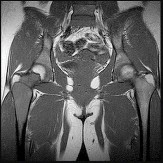

This patient has a dedifferentiated liposarcoma within a preexisting atypical lipomatous tumor. The imaging demonstrates a large fatty mass with increased internal septations proximally (the atypical lipomatous tumor) and a solid enhancing mass distally (the dedifferentiated portion). A biopsy reveals a high-grade liposarcoma. The other diagnostic responses do not reflect sarcomatous transformation of the lesion.

Surgical treatment of a high-grade sarcoma involves wide surgical resection. Radiation decreases local recurrence but does not clearly influence overall survival. The role of chemotherapy in high-grade soft-tissue sarcomas remains investigational; there is a modest (8%-15%) associated improvement in overall survival.

Intramuscular lipomas and atypical lipomatous tumors are treated with marginal resection alone. Radiation therapy for soft-tissue sarcomas may be given before or after surgery. When administered before surgery, patients have a higher wound complication rate but better long-term function attributable to lower rates of lymphedema, fibrosis, and contractures.